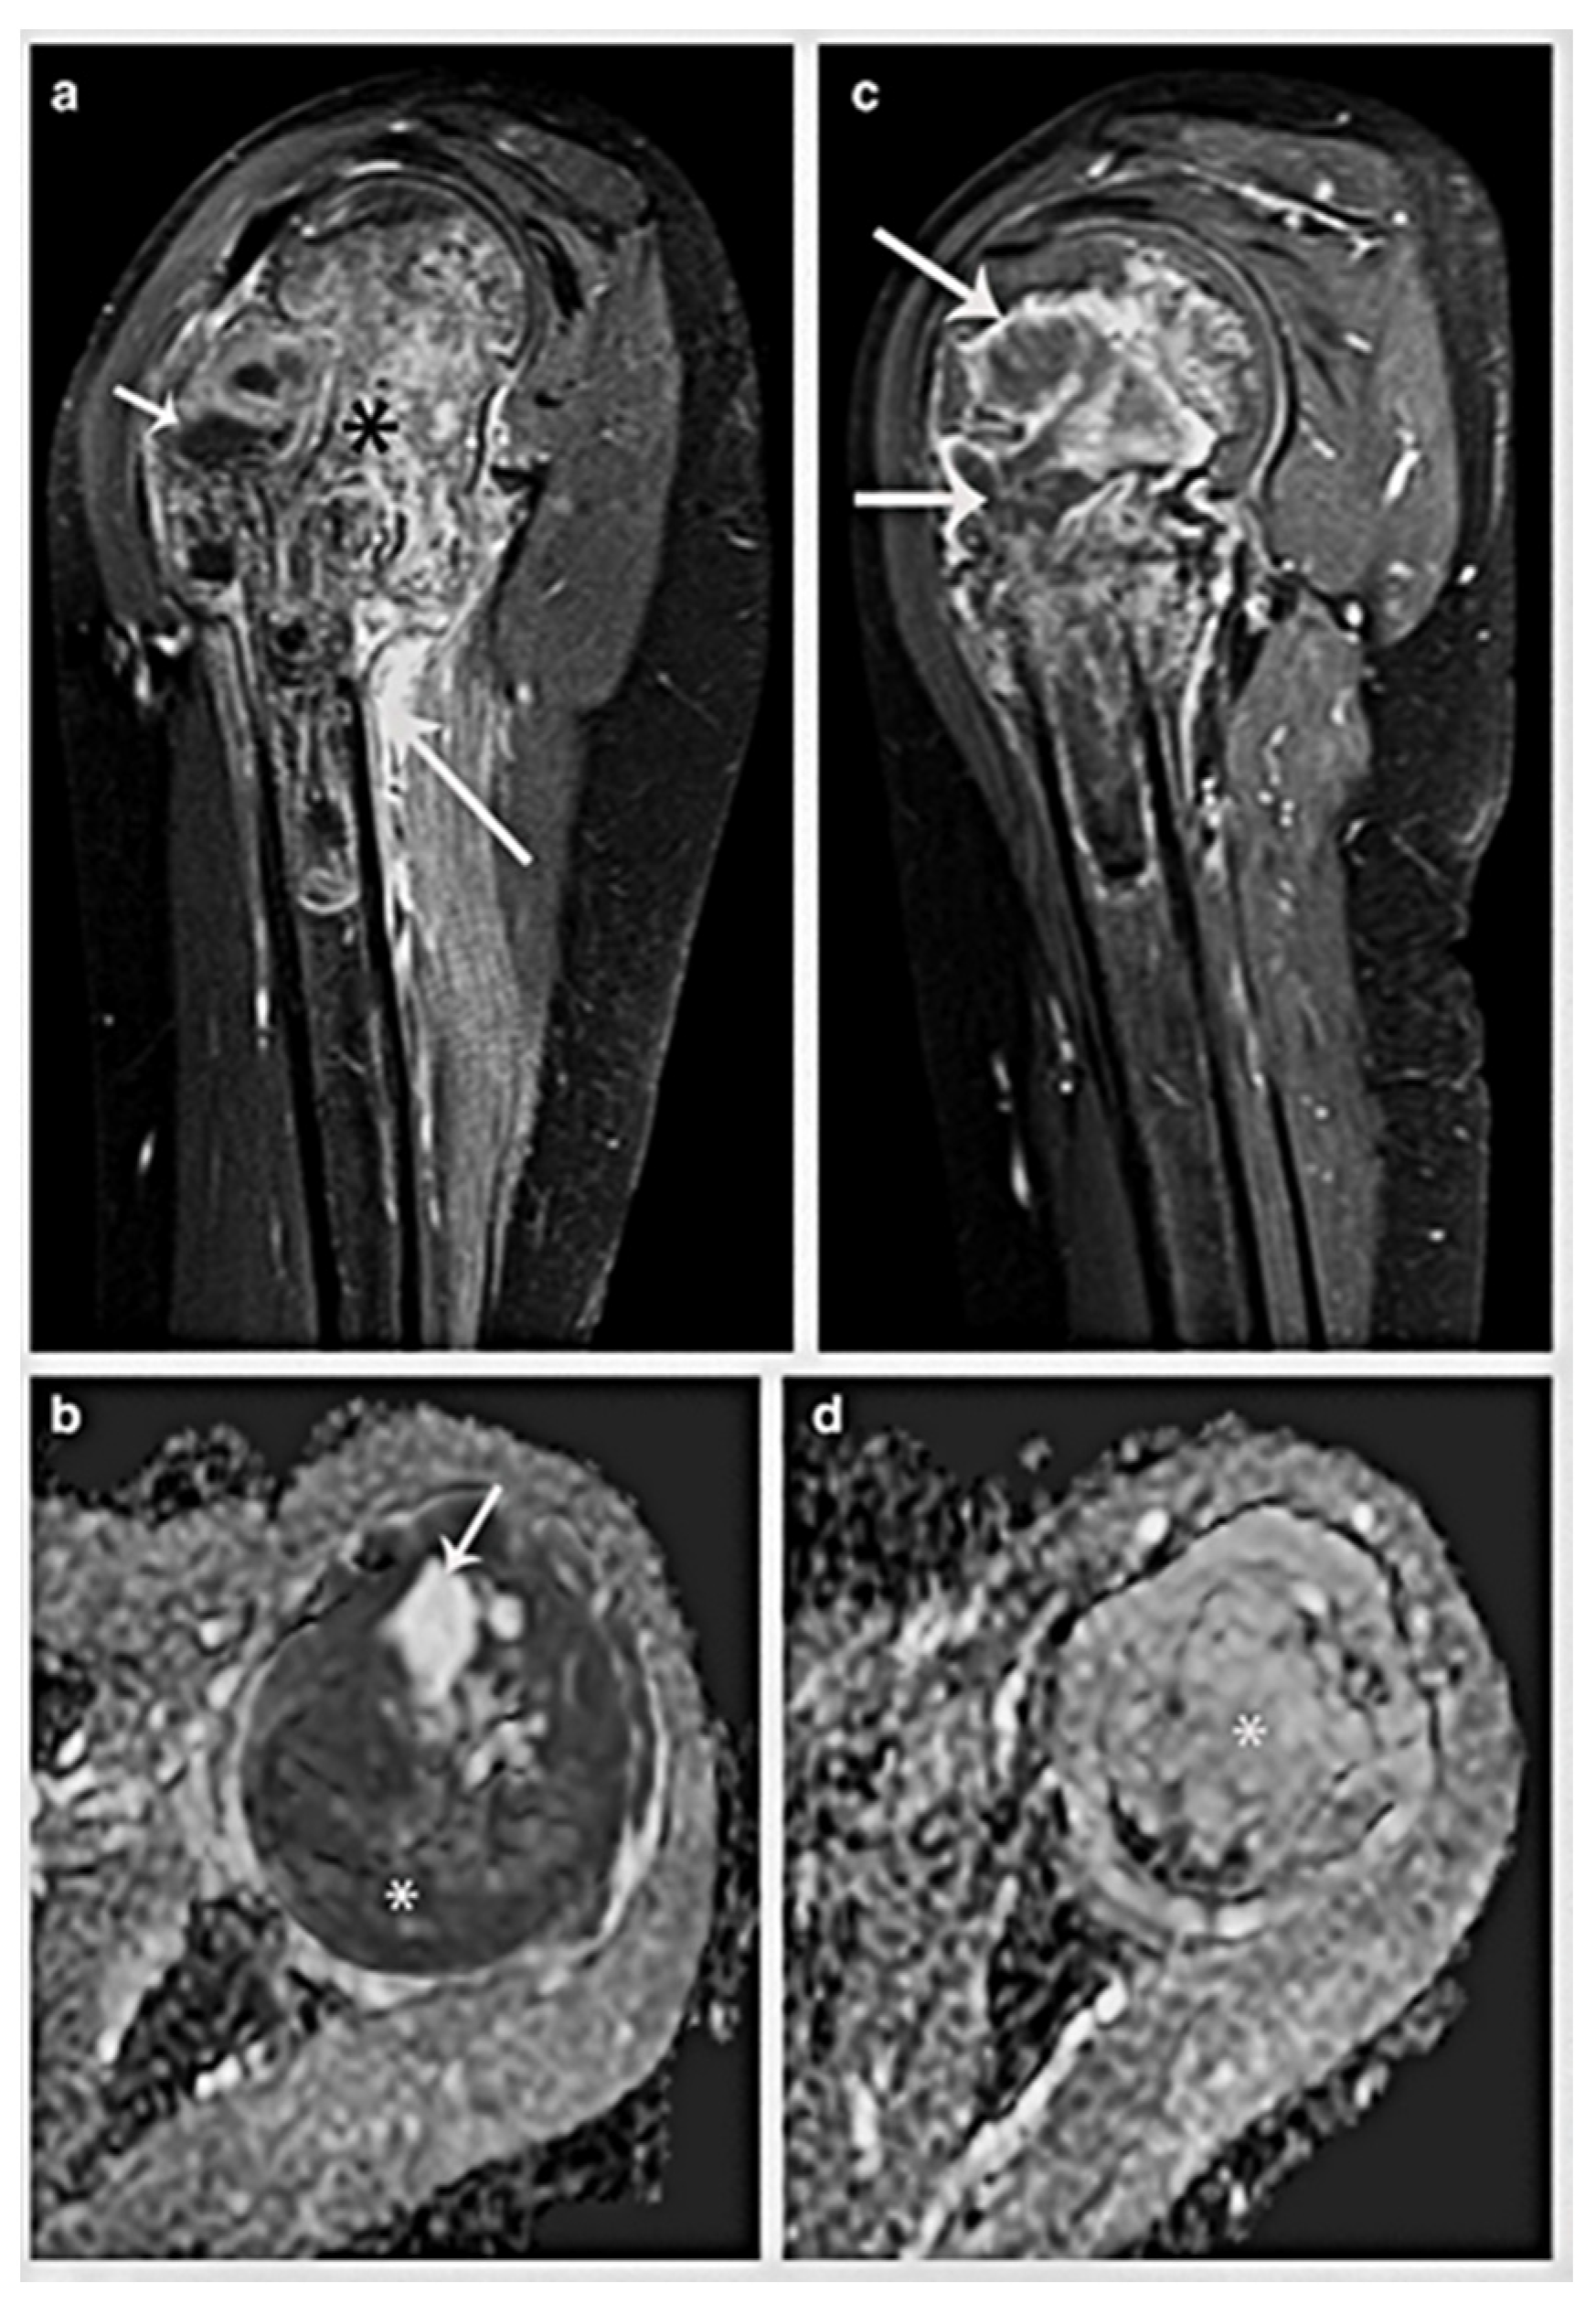

Figure 5. A 13-year-old boy has osteosarcoma affecting his proximal metaphysis of the tibia. (a) Soft-tissue mass (arrow) and a heterogeneous bone lesion (*) are seen on a coronal fat-suppressed T2-weighted MR picture. (b) The tumour’s diffusion restriction (*) is visible in the axial ADC MR picture. (c,d) MRI after chemotherapy. (c) A peripheral hypointense rim in the tumour that suggests calcification can be seen on the coronal fat-suppressed T2-weighted MR image (arrow). (d) When compared to the original research, the axial ADC MR image demonstrates a reduction in the diffusion restriction areas (*), suggesting a positive response to treatment. Narejos Clemente et al. [35].

Patients with conventional osteosarcoma often undergo two courses of neoadjuvant chemotherapy before surgery [34]. A positive response to therapy is linked to a greater proportion of chemonecrosis, as observed in histopathological examinations. A good response to treatment is frequent, along with less tumour development and better clinical signs. Unlike soft-tissue tumours, osteosarcomas rarely exhibit significant shrinkage. Instead, numerous clinical studies have shown that decreased growth rates and intralesional ossification function as surrogate indicators of therapeutic response (Figure 5).